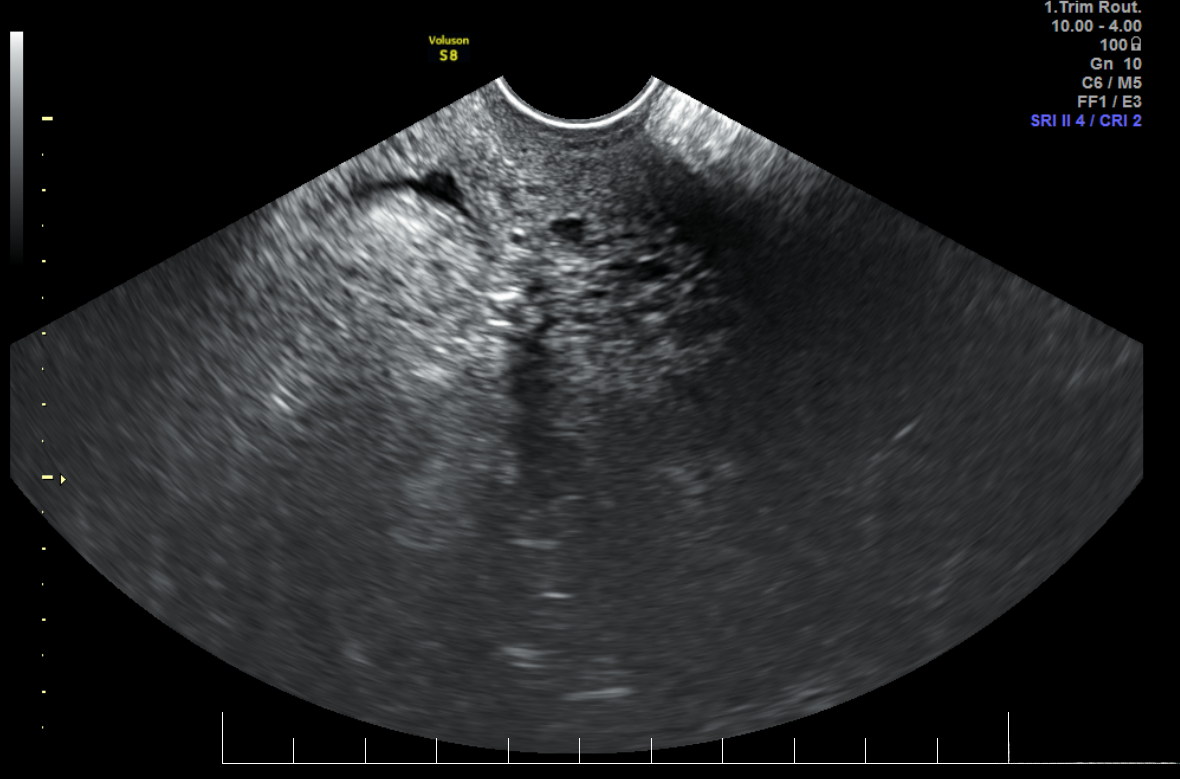

4. 超声成像

工作原理 : 超声成像利用高频声波(超声波)来成像。超声波通过探头发射进入人体,不同密度的组织反射的声波不同,探头接收这些反射波并形成图像。由于其非侵入性和无辐射,超声成像被广泛应用。

成像技术 :

- B超(Brightness Mode) :最常见的模式,显示二维灰度图像。适用于大多数的常规超声检查。

- 多普勒超声 :利用多普勒效应检测血液流动,评估血管和心脏功能。适用于血流动态检测。

- 3D/4D超声 :三维超声图像和实时四维成像,特别用于胎儿检查。提供更直观的解剖图像。

应用 :

- 妇产科:孕期胎儿发育监测 :无辐射成像,适合孕妇和胎儿的安全检查。

- 心脏病学:心脏结构和功能评估 :实时动态成像,有助于评估心脏功能和病变。

- 腹部检查:肝脏、胆囊、肾脏等器官 :高分辨率成像,有助于腹部器官的评估。

- 血管检查:动脉和静脉的血流评估 :无创检查,提供血管动态信息。